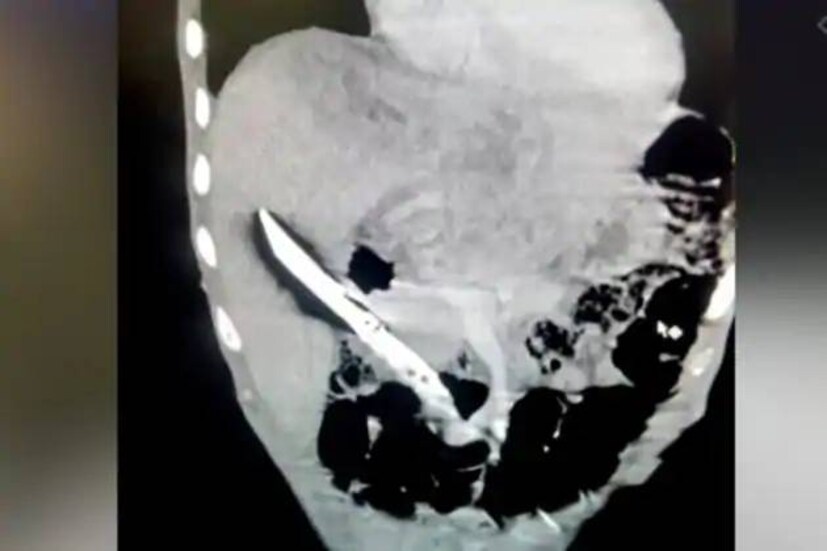

Shocking | വയറുവേദനയുമായി ആശുപത്രിയിലെത്തിച്ച യുവാവിന്റെ കരളിൽ തറഞ്ഞിരുന്നത് കത്തി!

ഇനി കത്തി എങ്ങനെ യുവാവിന്റെ വയറ്റിലെത്തി എന്നതാണ് ഏവരെയും ആശ്ചര്യപ്പെടുത്തുന്ന കാര്യം. ഇതേക്കുറിച്ച് ഒടുവിൽ യുവാവ് തന്നെ വെളിപ്പെടുത്തി. താൻ കത്തി വിഴുങ്ങുകയായിരുന്നുവെന്ന് ഇയാൾ സമ്മതിച്ചു. ഇയാൾ നേരത്തെയും മൂർച്ഛയേറിയ വസ്തുക്കൾ വിഴുങ്ങിയിട്ടുണ്ടെന്ന് വ്യക്തമായിട്ടുണ്ട്. ബോർഡ് പിൻ, സൂചി, മത്സ്യബന്ധനത്തിന് ഉപയോഗിക്കുന്ന ചൂണ്ട എന്നിവ ഇയാൾ നേരത്തെ വിഴുങ്ങിയിട്ടുണ്ട്. അപ്പോഴൊക്കെ വിദഗ്ദ്ധ ചികിത്സയിലൂടെയാണ് ഇയാൾ ജീവിതത്തിലേക്ക് മടങ്ങിയെത്തിയത്. എന്നാൽ ഇത്രയും വലുപ്പമുള്ള കത്തി വിഴുങ്ങിയത് ഡോക്ടർമാരെ പോലും ഞെട്ടിച്ചു. മണിക്കൂറുകൾ നീണ്ട ശസ്ത്രക്രിയയിലൂടെയാണ് കത്തിന് നീക്കം ചെയ്യാനായത.

പിത്തസഞ്ചിക്കും ധമനിക്കും ഇടയിൽ കത്തി അപകടകരമായി കുടുങ്ങിയതായി എയിംസിലെ ഡോ. എൻ ആർ ദാസ് പറഞ്ഞു. അത്തരം സന്ദർഭങ്ങളിൽ, ശസ്ത്രക്രിയയിൽ സൂക്ഷ്മതയില്ലെങ്കിൽ അയോർട്ടയ്ക്ക് കേടുപാടുകൾ സംഭവിക്കുകയും കനത്ത രക്തസ്രാവം മൂലം രോഗി മരിക്കുകയും ചെയ്യും. അതിനാലാണ് ശസ്ത്രക്രിയ ഏറെ സങ്കീർണമായത്. ഡോക്ടർമാർ അന്നനാളം ഭിത്തി മുറിച്ച് കരളിൽ നിന്ന് കത്തി നീക്കം ചെയ്യുകയായിരുന്നു.